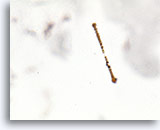

Figure 156

Ferruginous Body

Ferruginous bodies due to asbestos fibers typically have a clear central core.

Ferruginous Body

Ferruginous bodies due to asbestos fibers typically have a clear central core.

Figure 156

Ferruginous Body

Ferruginous bodies due to asbestos fibers typically have a clear central core.

Ferruginous Body

Ferruginous bodies due to asbestos fibers typically have a clear central core.